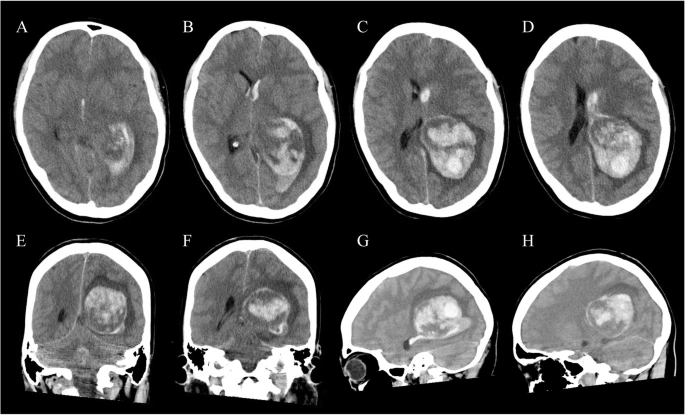

Layering or hematocrit level or differential density within an acute intraparenchymal bleed on CT? Think: 1. coagulopathy 2. anticoagulants 3. Tumor-related bleed 4. evolving /expanding hematoma with active bleed. —On-call pearls from my reporting list

Layering or hematocrit level or differential density within an acute intraparenchymal bleed on CT?

Think: 1. coagulopathy  2. anticoagulants 3. Tumor-related bleed 4. evolving /expanding hematoma with active bleed.

—On-call pearls from my reporting list